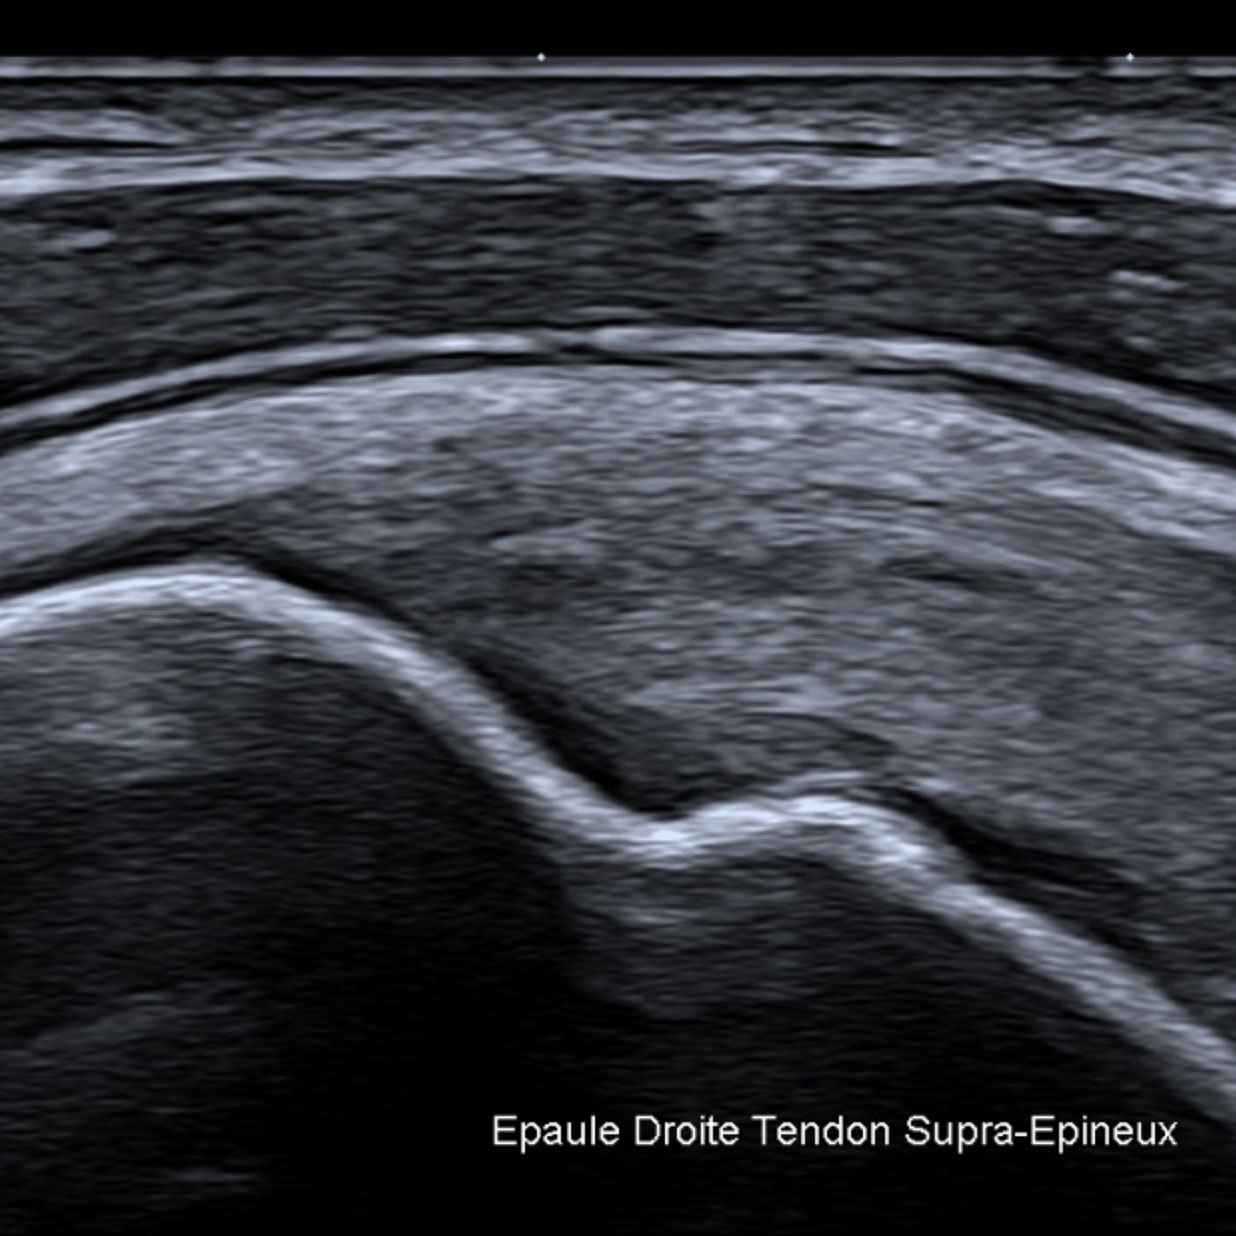

Pour exemples, les liquides purs apparaissent noirs (anéchogène) sur l’écran. Les tissus ou les liquides épais (mucoïde, hématome) apparaissent gris, les calcifications tout comme le gaz et l’air réfléchissent complètement les ultrasons et sont visibles sous la forme d’une ligne blanche sans aucun écho sous-jacent.

Pendant l’examen le médecin réalise plusieurs clichés et les images sélectionnées sont imprimées et jointes au compte rendu. Elles n'ont qu'un rôle d'illustration, la qualité de la reproduction ne permettant en aucun cas de réévaluer, par exemple, un diagnostic.

GALERIE PHOTOS